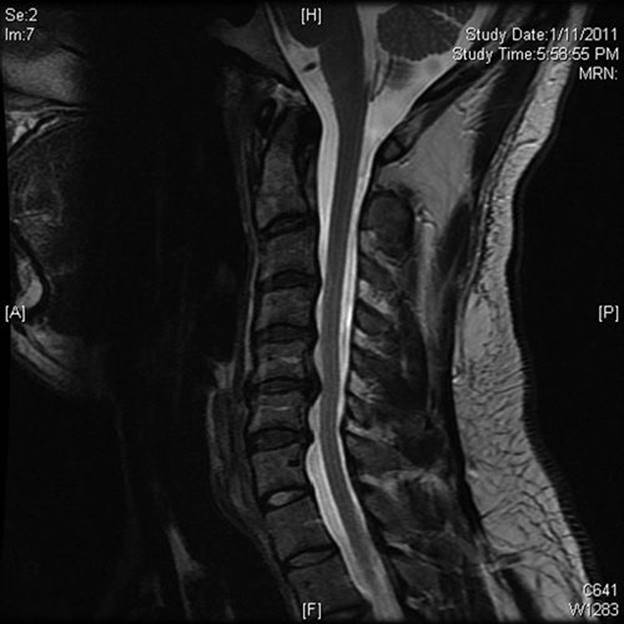

b. MRI scan (Fig. 22.2). It is excellent for demonstrating nerve-root compression and cord compression from bone spurs. It does not provide as much detail about bone anatomy as the CT scan.

FIGURE 22.2 Sagittal MRI of the cervical spine demonstrating multiple-level spondylosis.